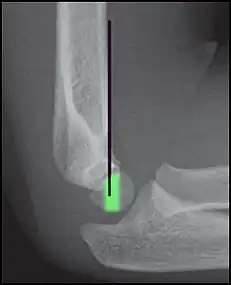

Anterior and posterior sail sign in a child who has a subtle supracondylar fracture -

Anterior humeral line (black line), with normal area passed on the capitulum of the humerus colored in green in a 4 year old child.[9] -